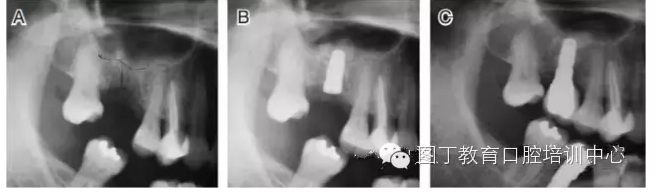

病例1 骨質(zhì)較充裕(圖3)

圖3